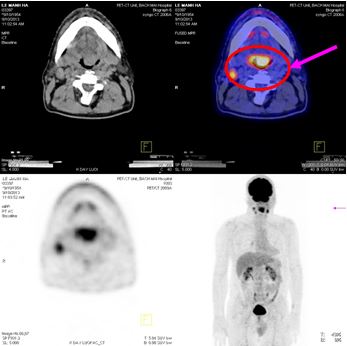

Trên hình ảnh PET/CT:

- Vùng đáy lưỡi có khối lớn kéo dài đến thanh quản kích thước: 2,4x3,6x2,9cm, tăng hấp thu F18- FDG max SUV=8,28.

- Hạch góc hàm trái kích thước: 1,9cm, tăng hấp thu F18- FDG max SUV=6,89. Hạch góc hàm phải kích thước: 1,8cm, max SUV=5,28. Hạch cảnh giữa phải kích thước: 1,3cm, max SUV=4,42.

Hình 3. Hình ảnh khối u vùng đáy lưỡi di căn hạch cổ hai bên trên hình ảnh PET/CT